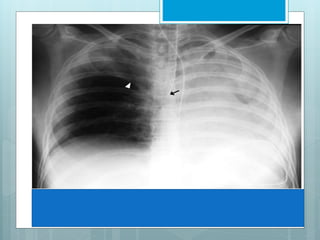

Signs Of RUL Collapse

 S Sign of Golden.

S Sign of Golden - Refers to reverse

"S" shape of minor fissure in RUL

collapse due to a central obstructing

mass. Sup portion of "S" form displaced

minor fissure, while inf. portion results

from mass itself.